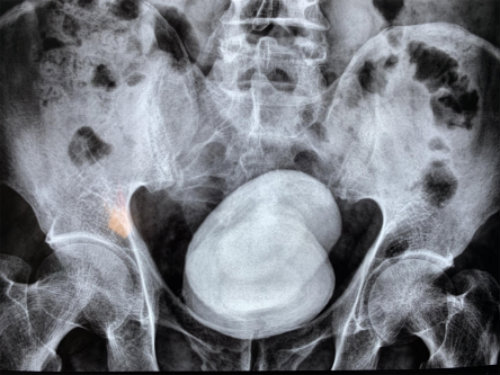

經(jīng)查,鄭先生的膀胱被兩顆直徑長(zhǎng)達(dá)七八公分的結(jié)石充滿(mǎn),從X光片上看,這對(duì)超大號(hào)結(jié)石就像一對(duì)“雙胞胎”,霸占著他的膀胱。因結(jié)石巨大,醫(yī)生只能采用膀胱切開(kāi)取石的方法將石頭取出。當(dāng)醫(yī)生把兩個(gè)拳頭大的結(jié)石拿給他看時(shí),他對(duì)自己久拖不治的行為懊悔不已。